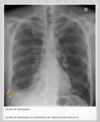

Quelles sont les 4 investigations pertinentes au diagnostic d’un épanchement pleural?

- Radiographie thoracique (++)

* Si la radiographie debout ne permet pas de déterminer le type d’épanchement, opter pour une radiographie en décupituse latéral, une TDM du thorax ou une échographie *

Quels sont les signes radiologiques de l’épanchement pleural?

- Le liquide s’accumule à la portion inférieure de la cavité pleurale.

- Le lieu de l’épanchement sera blanc

- Présence d’une courbe de Damoiseau (ligne en ménisque, bombé par intérieur et non comme une coupole)

- Signe de la silhouette avec la coupole

- Émoussements des récessus costo-diaphragmatiques (perte de l’angle aigu habituel)